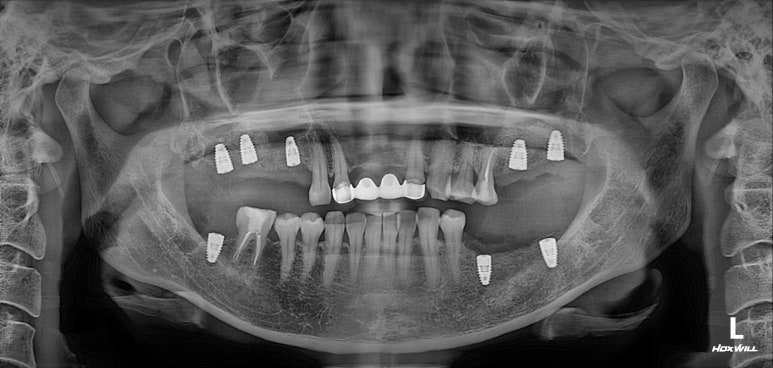

드디어 치료가 마무리 되는 날!..

마지막에 심었던 오른쪽 위 어금니 임플란트 골유착이 완성되었고, 그동안 나머지 부위들은 임플란트 크라운 치료를 완료 해두었습니다.

상당히 깔끔하게 제작되었고, 기존에 해둔 상악동 뼈이식술도 아주 잘 자리잡아주었네요.

그렇게해서 최종완료 후 치과용 파노라마 사진입니다!

치과치료에 대해 잘 모르시는 분이라 할지라도 보고 있으면, 치료가 조화롭게 잘 끝났구나.. 라고 아실 수 있으리라 생각합니다.

제가 제일 좋아하는 치과용 파노라마 비교 사진입니다.

앞으로 나란히를 한 것 같이 평행한 임플란트의 완성도는 항상 카타르시스를 느끼게 합니다.

정말 어디하나 나무랄 것 없이 치료가 잘 마무리되었는데, 물론 정말 열심히 정성들여 수술하는 저도 칭찬받아야 마땅하지만 늘 묵묵히 열심히 크라운 치료를 잘 해주는 우리 보철과 전문의 원장님들께 그 공을 돌리고 싶습니다.